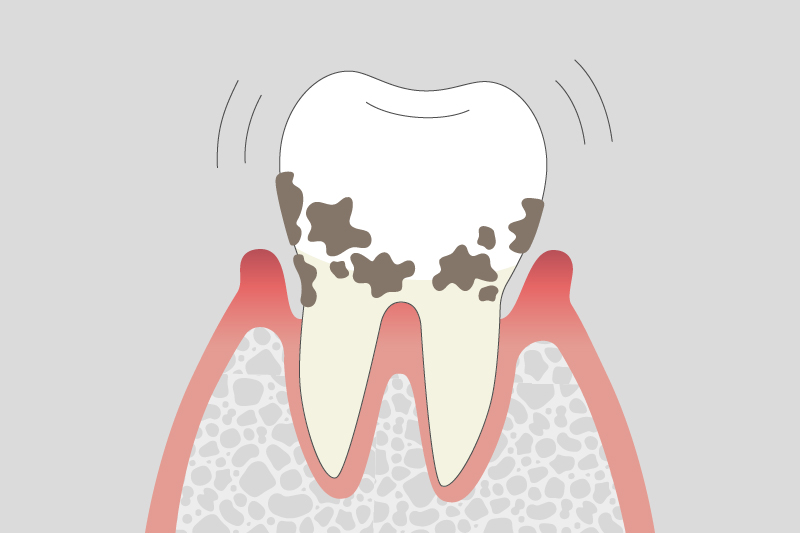

03.

中等度歯周病

炎症が進み、歯を支える骨の吸収が拡大する。歯がグラつくことがあります。